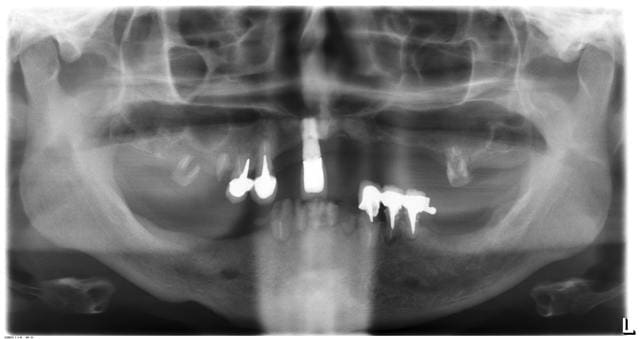

D'après vous : fraise chir + davier ou on laisse + vis de couverture.

Sachant qu'on va faire un complet sup traditionnel.

Donc le problème principal ici c'est l'implant ?

ne surtout pas laisser

tu aurais une zone generant une instabilité de ta prothèse

par contre ... on ne sait jamais s'il n'y aura pas besoin d'utiliser des trepans (le quelques spires integrées peuvent l'être vraiment)

a adresser à un implanto aguerri